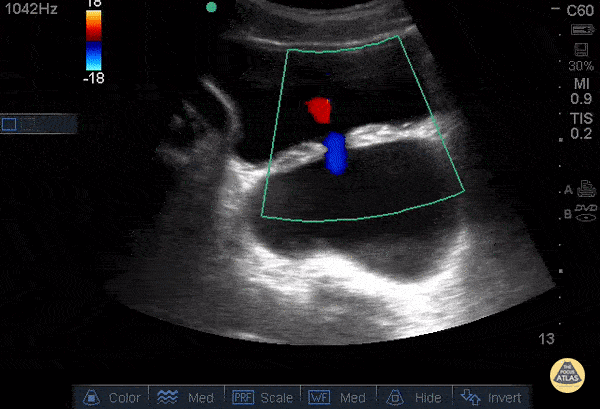

78 yo M h/o BPH s/p TURP 1yr ago presents c/o difficulty voiding x2 wks. US of bladder revealed 2 large fluid filled (anechoic) structures w/ a communicating tract and bidirectional flow on color Doppler. The superficial structure is the urinary bladder while the deep structure is a large bladder diverticulum. Pt didn't have any previously documented hx of a bladder diverticulum. A bladder diverticulum is a rare congenital or acquired defect consisting of a protrusion of the mucosa through the bladder musculature. The most common acquired cause is bladder outlet obstruction 2/2 to BPH. Pts w/ a new diagnosis in the ED should be referred for urology follow up. These pts are at high risk of UTIs and bladder calculi due to urinary stasis from incomplete emptying of the diverticulum. This can even occur in pts w/ a Foley, as the catheter may not drain the diverticulum. In fact, having a chronic indwelling catheter is a rare cause of bladder diverticula. Pts w/ hematuria, lower urinary tract symptoms, recurrent UTIs, or bladder calculi may require diverticulectomy. Drs. Justin Berkowitz, Adrian Aurrecoechea, and Catherine Bon